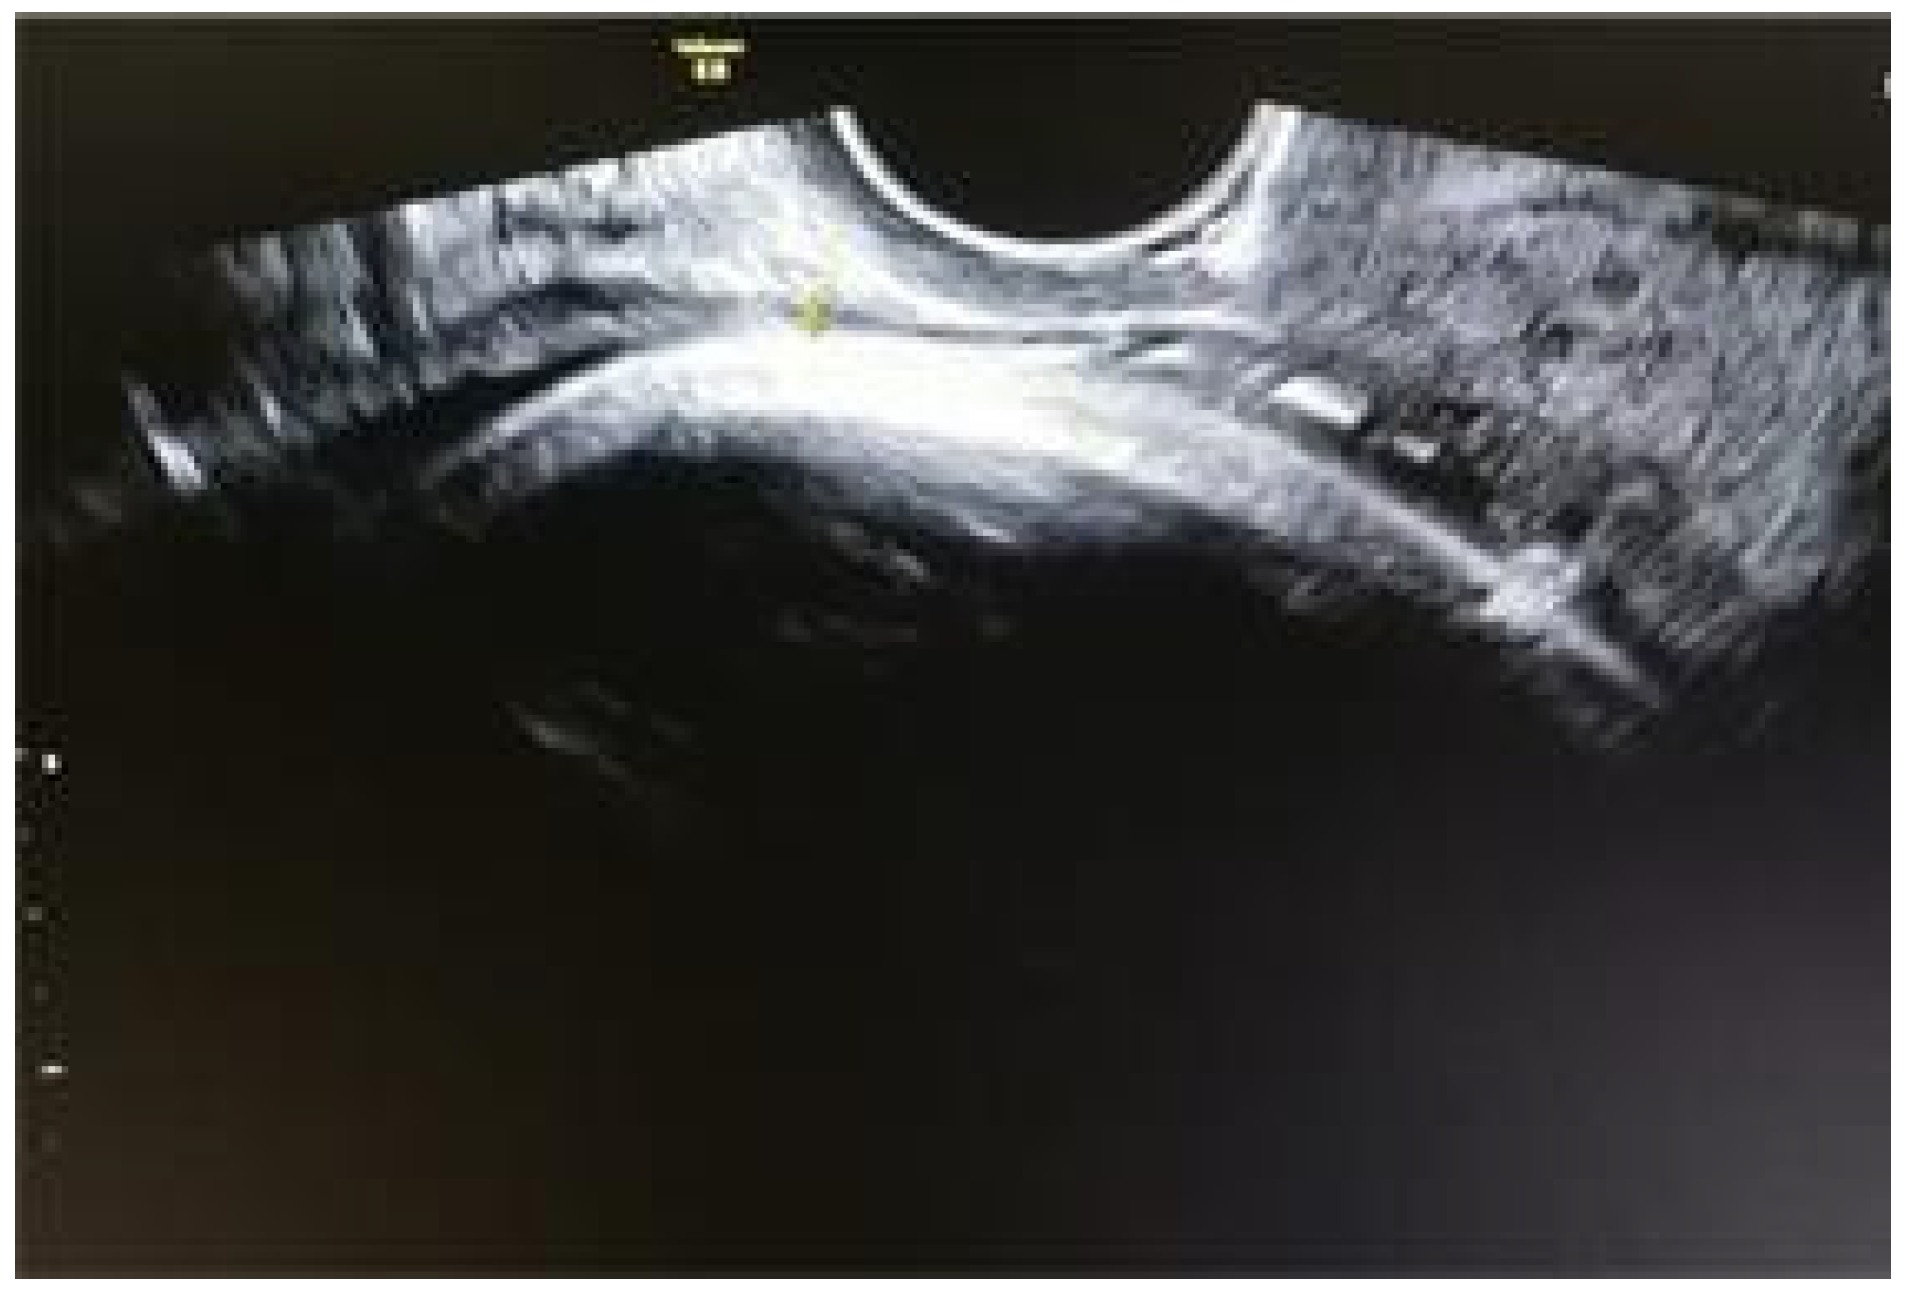

- The predictive ultrasound parameters for the risk of rupture/dehiscence of the uterine scar showed varying cut-off values, ranging between 2.0 and 3.5 mm for the lower segment and up to 0.97 mm for the myometrium.

- This observation of inverse proportionality between the uterine thickness and the risk of rupture/dehiscence of the scar seems to be correlated with the histopathological features of the cesarean section scar.